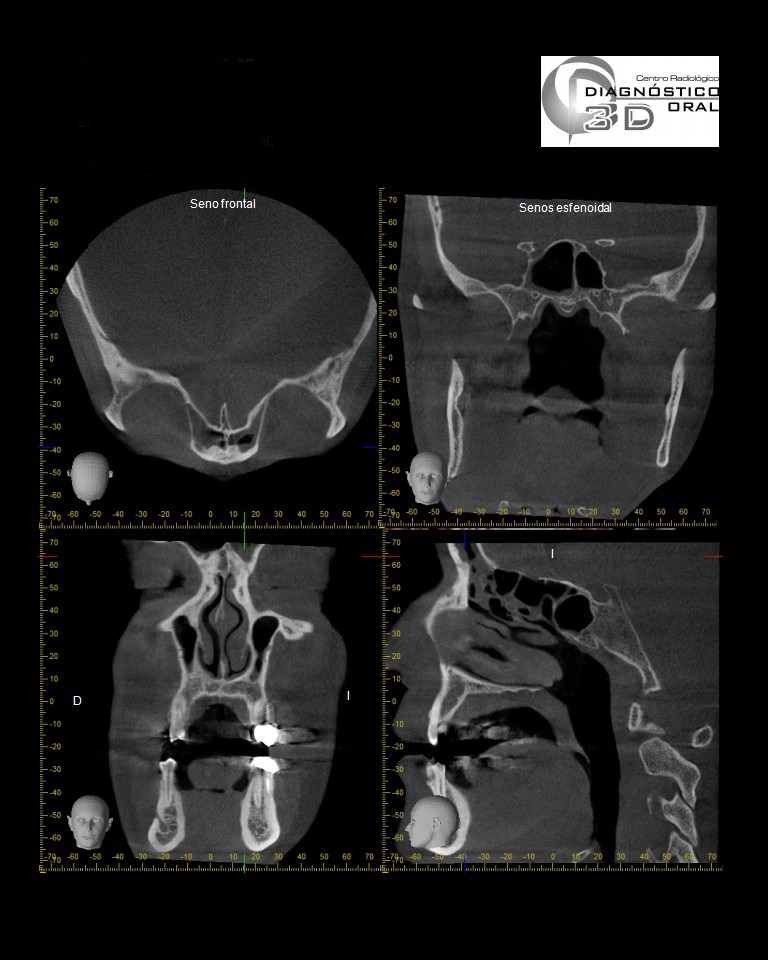

El Centro Radiológico Diagnóstico Oral 3D, es una empresa antioqueña que ofrece a sus pacientes desde el año 2009, tecnología de vanguardia en radiografías tridimensionales con calidad fotográfica. Las posibilidades para mejorar la eficacia en los diagnósticos bucales son evidentes, también lo son las posibilidades de manipulación de imagen. El sistema de imágenes en 3D ofrece detalles sin precedentes, convirtiéndola en la opción idónea para la mayoría de aplicaciones odontológicas, incluyendo implantes, tratamiento de conductos, ortodoncia, odontopediatría, periodoncia y cirugía

El mayor beneficiado con el uso de esta tecnología es el paciente, el cual podrá ser evaluado en todas sus dimensiones con una baja dosis de radiación, con un costo accesible y sin contaminar  el medio ambiente. Dependiendo de la necesidad del paciente, hay varios tipos de tomografías y los especialistas en el área odontológica hacen uso de ellas según su especialidad.

La radiología oral especializada es fundamental para una práctica dental integral, proporcionando información específica que influye en la toma de decisiones clínicas y mejora los resultados del tratamiento para los pacientes

Evaluación de patologías dentales y maxilofaciales

Planificación de tratamientos ortodónticos y ortognáticos

Diagnóstico de traumatismos dentales y maxilofaciales

Detección de lesiones quísticas y tumorales

Evaluación pre y postoperatoria de cirugías maxilofaciales